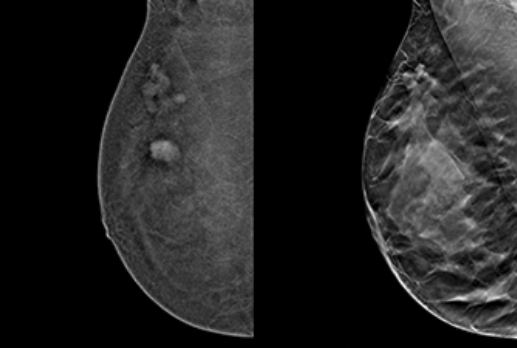

Dr. Eva Pallwein-PrettnerWomens ImagingMammography's landscape continues to evolve in EuropeWhen navigating the latest breast screening recommendations and the dynamic landscape in Europe, clarity is paramount for both patients and healthcare providers, writes Dr. Eva Pallwein-Prettner.October 18, 2024Page 1 of 1Top StoriesCTBelgian study shows AI's promise in coronary ischemiaA deep-learning model for assessing vessel-specific coronary ischemia performed well compared to invasive fractional flow reserve in a multicenter study published by European Radiology on 11 October.Artificial IntelligenceAI on the Aegean: EuSoMII congress comes to CreteDigital X-RayAI fracture detection tools tested head-to-headMolecular ImagingPSMA-PET/CT may replace NaF-PET/CT in advanced prostate cancerWomens ImagingWhat's the link between assisted reproduction and breast cancer?